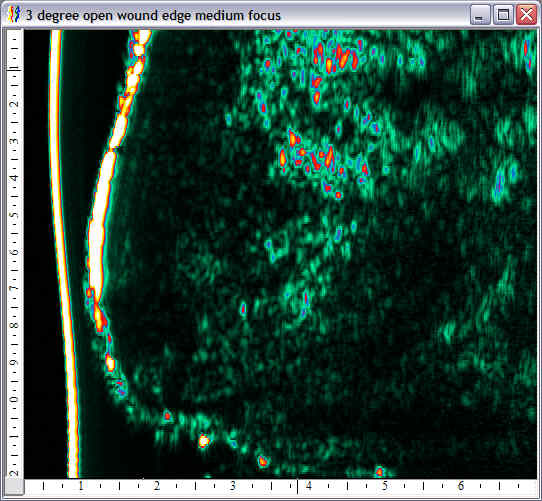

| Pressure wounds |  Pressure wound, edge |

Pressure wound, open |